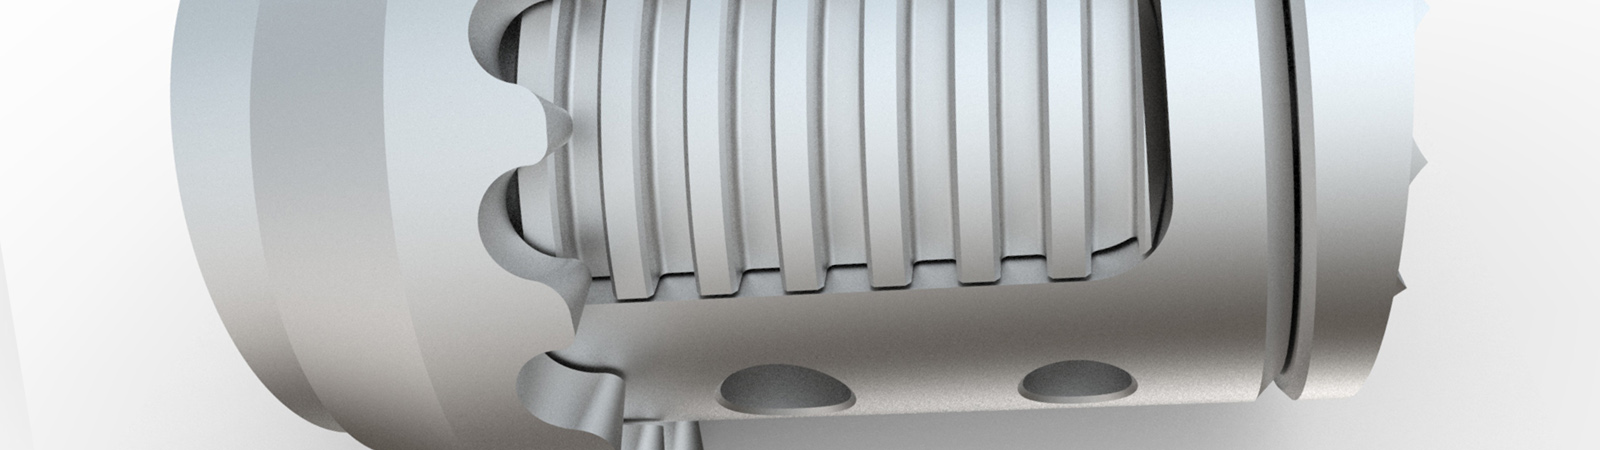

KINERA ist ein einzigartiges System auf dem Markt. Die Besonderheit liegt am Design des Schraubenkopfes. Medio-Lateral ist der Kopf schwenkbar. Kranio-Kaudal ist der Kopf fixiert. Durch den Einsatz einer Wippe im Schraubenkopf, welche sowohl den Stab von der unteren, als auch von der oberen Seite umschließt, wird die notwendige Flexibilität auch in Kranio-Kaudaler Ebene gewährleistet.

KINERA erlaubt bei osteoporotischem Knochen durch seine Fenestierungen im Gewindekörper eine feste Verankerung der Pedikelschraube mittels Zementinjektionen.Der Zement wird direkt über Applikationshülsen durch die Kanülierung der Schraube eingebracht. Am distalen Ende des Gewindes tritt der hoch visköse Zement durch die Fenestierung langsam in den trabekulären Strukturen des Wirbelkörpers aus.